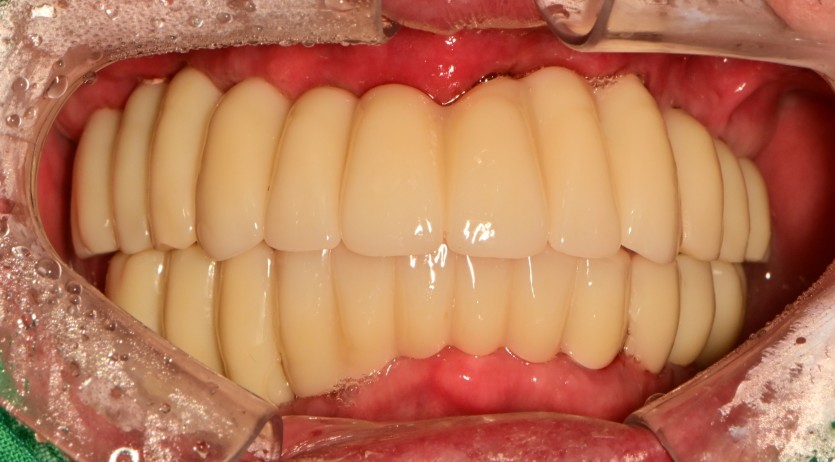

전체 임플란트 증례입니다.

18개의 임플란트로 완성하였습니다.